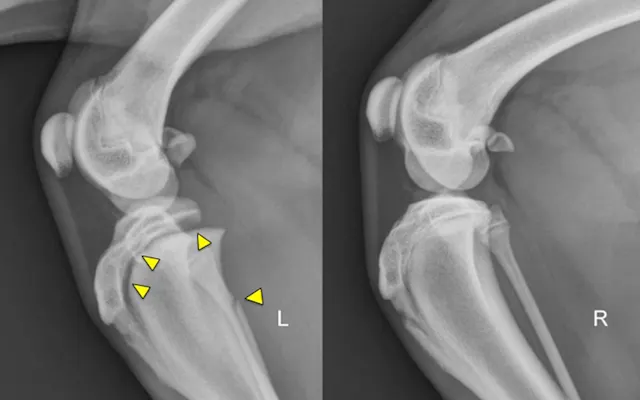

Physeal fractures can occur in any juvenile animal, even with little trauma, because the physis is weaker than the adjacent bone and ligaments. Orthogonal radiographs of any painful joint should be performed. Oblique projections, radiographs of the limb in different positions, and radiographs of the contralateral limb for comparison can all aid in the diagnosis of a physeal fracture. Shown here are lateral stifle radiographs from an 8-month-old mixed breed dog that presented for acute onset of lameness in the left pelvic limb after he slipped earlier that evening; pain was localized to the left stifle. Notice the open physes of the proximal tibia and distal femur, which are normal for a dog of this age. There is physeal separation and cranial displacement of the proximal epiphysis in the left tibia, and a greenstick fracture of the left fibula (arrows).